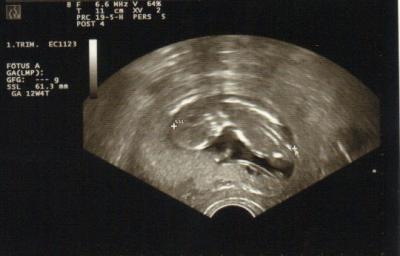

Dafür wächst der Bauch und das Zwerglein bewegt sich rege. Was ihm nicht schmeckt führt relativ schnell zu Schluckauf und Sodbrennen. Auch milde oder eher basische Lebensmittel führen dazu, mit Magensäure wohl nicht zu erklären. Der Bauch hat eine neue Dimension bekommen. Er it nun über den Hosenbund hinaus. Was dazu führt, dass man deutlich ein "zu schwer"-Gefühl bekommt.